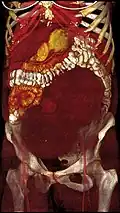

-

A very large (9 cm) fibroid of the uterus which is causing pelvic congestion syndrome as seen on CT -

A very large (9 cm) fibroid of the uterus which is causing pelvic congestion syndrome as seen on ultrasound -